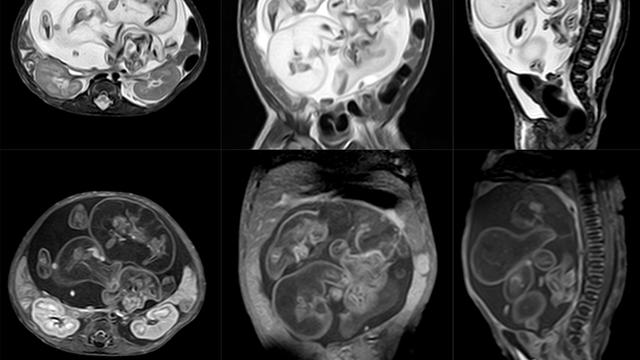

Deteksi kondisi ini seringkali dapat dilakukan melalui pemeriksaan ultrasonografi selama kehamilan. Pada hasil ultrasonografi, fetus in fetu biasanya muncul sebagai massa kompleks yang memperlihatkan batas yang jelas di dalam rongga perut bayi yang berkembang. Massa tersebut seringkali berisi kantong berisi cairan dengan elemen-elemen padat atau struktur tulang di dalamnya.

Bayi AA dirawat di RSUP M Djamil Padang untuk pemeriksaan medis lebih lanjut. Dalam pemeriksaan awal dengan CT scan, ditemukan tumor di dalam perutnya yang terdiri dari komponen padat, lemak, cairan, dan komponen tulang. Struktur di dalam tumor tersebut memiliki kemiripan dengan anggota tubuh, seperti kaki. Berdasarkan hasil radiologi, kasus ini digambarkan sebagai Fetus in Fetu, yang terjadi sangat jarang.